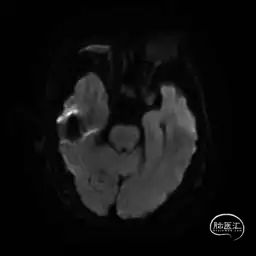

MRI提示小脑缺血性改变。

术后9天MRI: